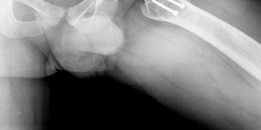

In the setting of coxa magna or severe cam deformity, the biomechanics of the hip are profoundly altered. The aspherical femoral head creates an abnormal center of rotation and leads to non-concentric articulation. During abduction, the enlarged lateral portion of the femoral head hinges against the lateral acetabular rim, a phenomenon known as hinge abduction. This hinging levers the medial femoral head out of the acetabulum, exponentially increasing contact pressures on the lateral compartment and leading to rapid articular cartilage degradation.

Radiographic evaluation must demonstrate a clear structural conflict, such as an extruded lateral head segment causing hinge abduction, but without advanced joint space narrowing. The presence of a "hinge" can often be confirmed dynamically under fluoroscopy or via abduction-internal rotation plain radiographs.

Standard radiographic series should include an anteroposterior pelvis, cross-table lateral, and false profile views of the affected hip. Functional views, such as maximum abduction and adduction radiographs, help quantify the degree of hinge abduction and the potential for concentric reduction.